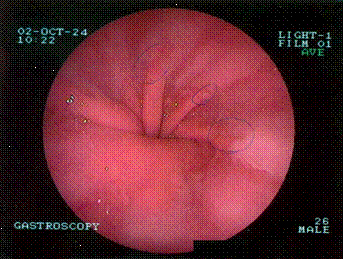

При проведении эндоскопического обследования

было обнаружено смещение линии пищеводно-желудочного перехода выше эзофагеального

кольца диафрагмы и пролабирование характерных продольных складок желудка в

пищевод, а также несостоятельность кардии.

участка диафрагмы соответствует области купола диафрагмы.) и гастроэндоскопии

(смещение линии пищеводно-желудочного перехода выше эзофагеального кольца

диафрагмы и пролабирование характерных продольных складок желудка в пищевод

(рис. 2), несостоятельность кардии). Был установлен окончательный диагноз -

врождённая параэзофагальная грыжа(congenitaherniaparaesophagealis).

Рис. 2.Эндоскопия. Пролабирование продольных

складок желудка в пищевод.